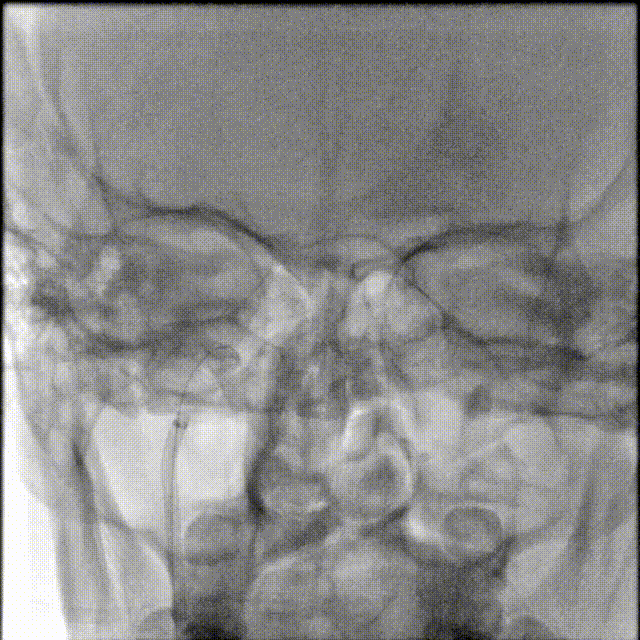

二.术前检查

术前CTA/CTP检查,动脉成像未见明显异常,平扫CT可见右侧横窦区域高密度、左侧顶叶片状高密度,窦汇区域、上矢状窦区域高密度充盈。随后紧急性头颅MRV检查,MRV提示上矢状窦及右侧横窦区域不显影。

1A

1B

1C

1D

1E

图注1:1A/1B 平扫CT可见右侧横窦、窦汇区域高密度,额顶叶片状高密度灶

1C 通路CTA检查动脉像未见特殊

1D/1E MRV冠状位及侧位可见上矢状窦及右侧横窦消失,左侧横窦乙状窦部分显影